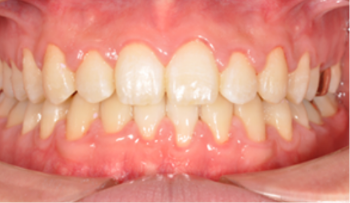

치아 교정은 바로 '교합'을 바로잡는 과정입니다.

단순히 삐뚤어진 치아를 가지런히 하거나 튀어나온 입을 넣는 것이 아니라,

위아래 턱뼈의 관계를 정상화하고 바르게 씹고 발음할 수 있도록 도와줍니다.

그 결과, 기능을 회복하고 아름다운 얼굴 모양을 완성할 수 있습니다.

결국, 교정 치료란 치아 기능을 회복해 균형 잡힌 아름다움을 만드는 일입니다.